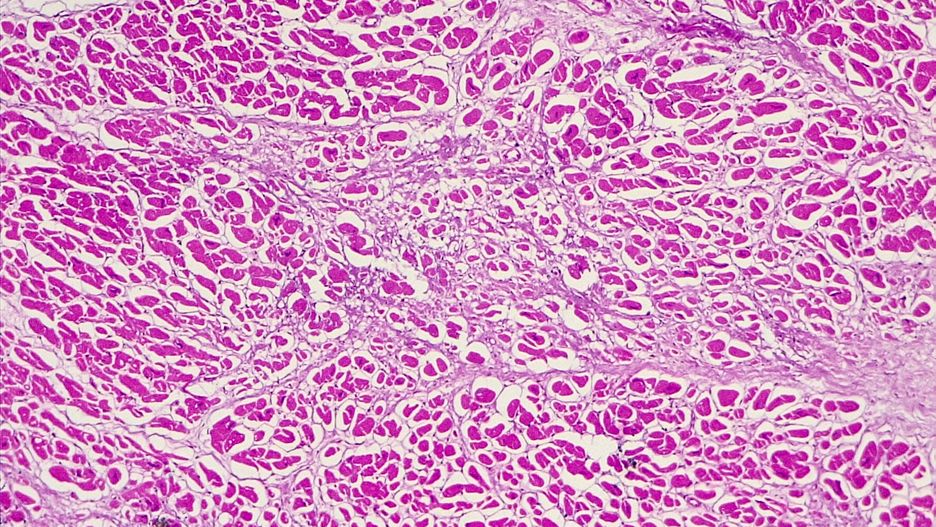

Mięsień serca pod mikroskopemMięsień serca pod mikroskopem

Źródło zdjęć: © Getty Images | ©️xia yuan